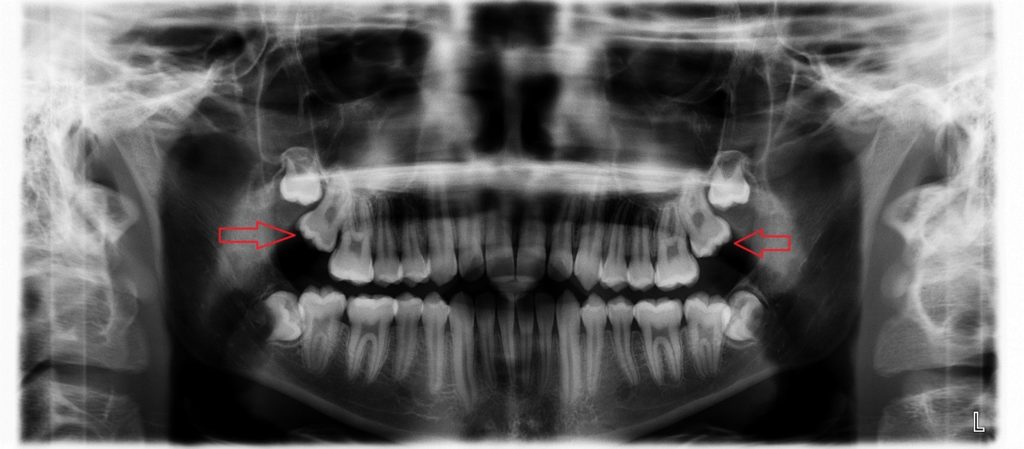

Impacted Wisdom Teeth (OPG) | Image | Radiopaedia.org

radiopaedia.orgImpacted Wisdom Teeth - City Dental Clinic

radiopaedia.orgImpacted Wisdom Teeth - City Dental Clinic

www.citydentalclinic.vnwisdom teeth impacted panoramic giudizio estrazione denti indicating sides

www.citydentalclinic.vnwisdom teeth impacted panoramic giudizio estrazione denti indicating sides

Panoramic Xray Showing Impacted Wisdom Teeth Stock Photo 1273167061

www.shutterstock.comImpacted Teeth Hi-res Stock Photography And Images - Alamy

An X-ray Showing Impacted Teeth Growing Irregularly On Both Ends Of The

www.temeculafacialoralsurgery.comImpacted Wisdom Tooth, X-ray Photograph By Scott Camazine